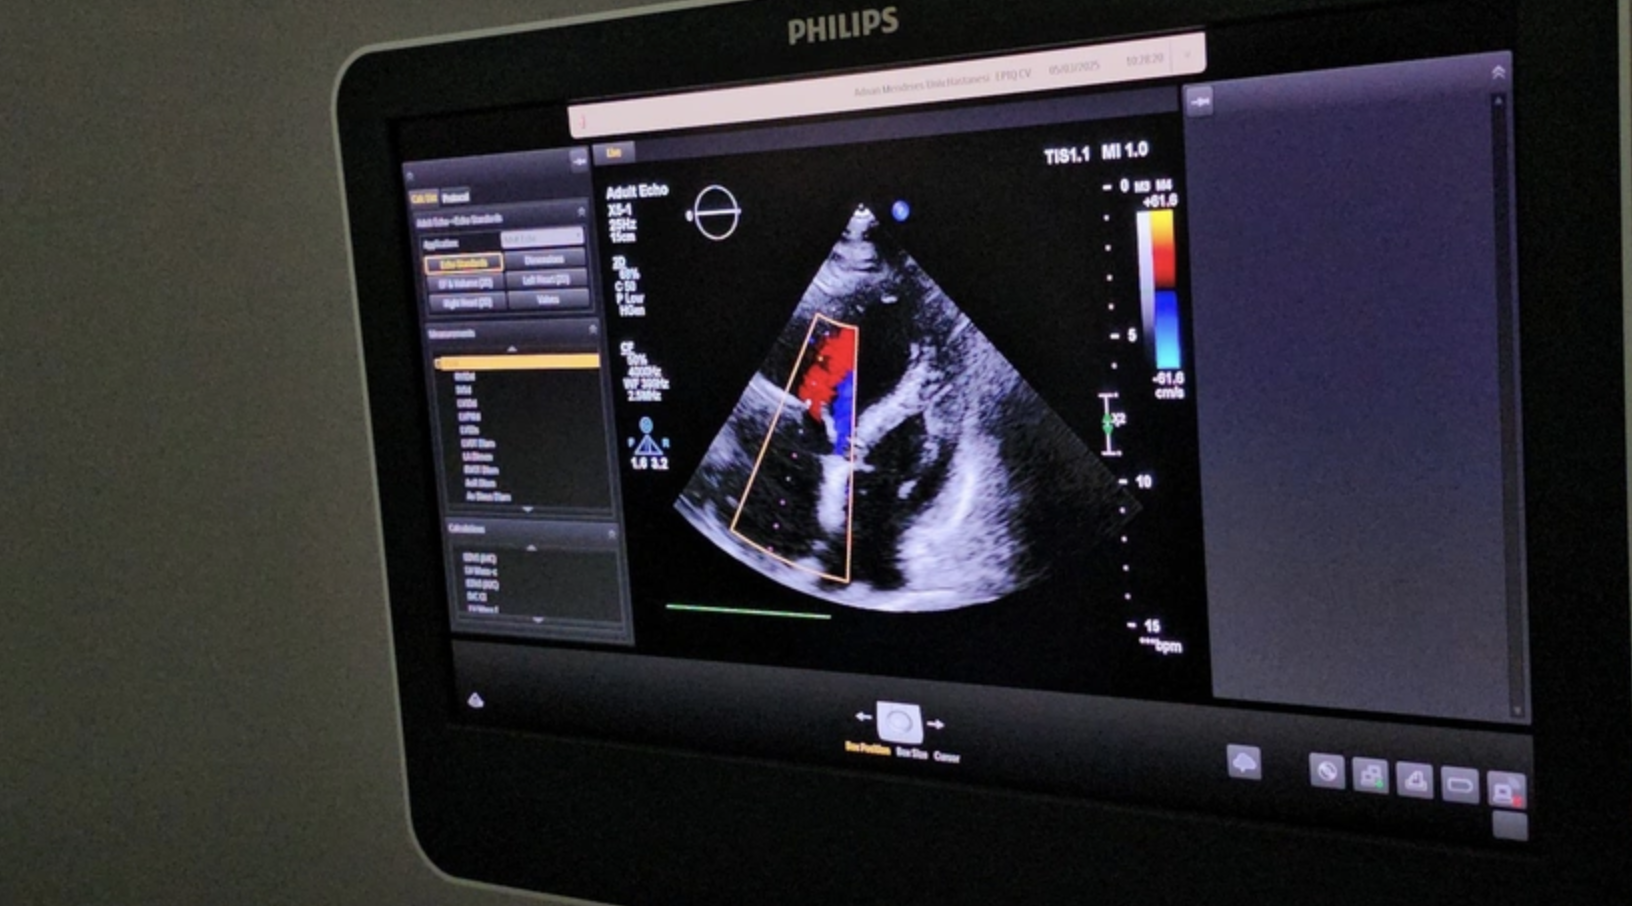

Aydın Adnan Menderes Üniversitesi (ADÜ) Hastanesi Başhekimi Prof.Dr.Mücahit Avcil öncülüğünde Kardiyoloji Ana Bilim Dalı öğretim Üyeleri Doç. Dr. Cemil Zencir ve Dr. Öğr. Üyesi Sevil Gülaştı, Türkiye'de ilk kez uygulanan bir yöntemle, kalbe kadar ulaşan yabancı cismi ameliyatsız olarak çıkardı.

Hastanın durumu hakkında bilgi veren Dr. Öğr. Üyesi Sevil Gülaştı, daha önce kifoplasti-vertebroplasti işlemi geçiren hastanın kullanılan dolgu maddesinin (sement) damarlara sızarak pulmoner emboliye neden olduğunu ve bunun hayati risk taşıyan ciddi bir durum oluşturduğunu belirtti. Gülaştı, "Hastamız tekrarlayan nefes darlığı şikâyetiyle sık sık acil servise başvuruyordu. Yapılan tetkiklerde vertebroplastide kullanılan polimetilmetakrilat maddesinin toplardamarlara sızarak kalbe kadar ulaştığını tespit ettik. Bu durumun tekrarlayan pulmoner embolilere neden olması üzerine hastayı multidisipliner bir yaklaşımla değerlendirdik" dedi.

İlk aşamada cerrahi yöntem düşünülse de, hastanın yüksek risk taşıması nedeniyle özel olarak modifiye edilen bir kateter ile sağ boyun toplardamarından girilerek yabancı cismin kapalı yöntemle çıkarılmasına karar verildiğini ifade eden Doç.Dr. Cemil Zencir, "Hastamızın durumu birçok branşla değerlendirildi. Bu tür girişimlerde hastanın güvenliği önceliklidir. Sementin mukavemet gücünü değerlendirdikten sonra uygun yöntemi belirledik ve kapalı bir teknikle tek parça halinde çıkardık.